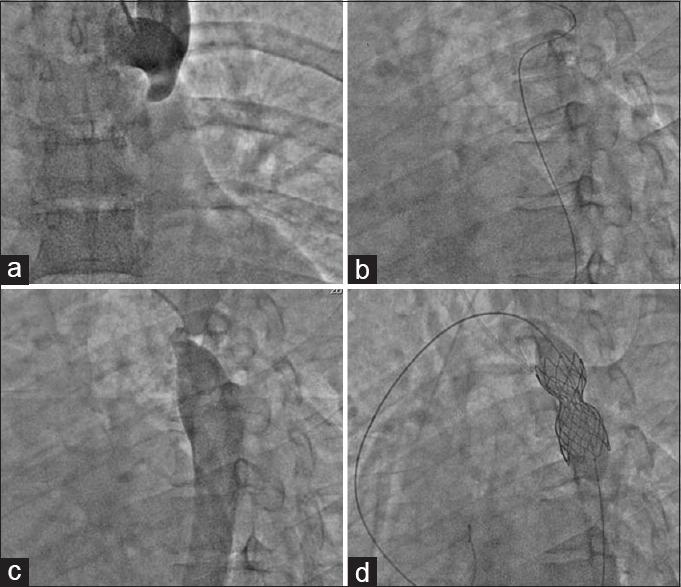

Coarctation of aorta (CoA) is one of the common congenital heart diseases. The two approaches for intervention in CoA include surgical and transcatheter (TC). Out of the two TC interventions available, stenting has been proved better than balloon angioplasty. We have two types of stents; the conventional ones - balloon expandable and the covered stent grafts. The elective covered stent implantation in all CoA has not offered any advantage. However, there are peculiar situations, apart from acute aortic complications, when they should be considered the first choice. We describe our experience of three cases of coarctation stenting, in which covered stenting should have been the preferred choice. A 32-year-old female with Turner's syndrome and severe CoA developed dissection after balloon angioplasty which was successfully managed with a covered stent. A 27-year-old female with near atresia of aorta was managed with balloon expandable stent which remained underexpanded despite post dilatation. A 17-year-old girl with severe CoA and patent ductus arteriosus (PDA) was managed with balloon angioplasty for the CoA and Amplatzer Duct Occluder I for the PDA. However, she developed re-coarctation in 6 months which was managed with a covered stent. Not all CoA requires the covered stents, but there are certain "high risk" CoA which require covered stent as first choice.

主动脉缩窄(CoA)是常见的先天性心脏病之一。CoA的两种干预方法包括外科手术和经导管介入(TC)。在现有的两种TC干预方法中,支架置入已被证明优于球囊血管成形术。我们有两种类型的支架,传统的球囊扩张式支架和覆膜支架移植物。在所有CoA患者中选择性植入覆膜支架并没有显示出任何优势。然而,除了急性主动脉并发症外,在某些特殊情况下,覆膜支架应被视为首选。我们描述了3例缩窄支架置入的经验,在这些病例中,覆膜支架置入本应是首选。一名32岁患有特纳综合征和重度CoA的女性在球囊血管成形术后发生夹层,使用覆膜支架成功治疗。一名27岁主动脉近乎闭锁的女性使用球囊扩张式支架治疗,尽管进行了后扩张,支架仍未完全扩张。一名17岁患有重度CoA和动脉导管未闭(PDA)的女孩,对CoA进行球囊血管成形术,对PDA使用Amplatzer动脉导管封堵器I进行治疗。然而,她在6个月后出现再缩窄,使用覆膜支架进行治疗。并非所有CoA都需要覆膜支架,但有某些 “高危” CoA需要将覆膜支架作为首选。